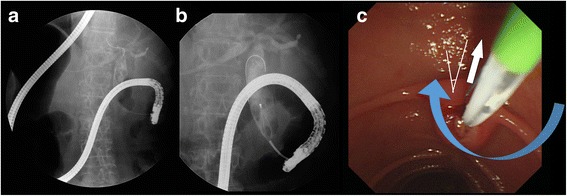

Two days later, we performed a second ERCP using a different method. The patient was again placed in a prone position with the endoscopist on the right side of the table. This time, the second portion of the duodenum was reached by following the lesser curvature, while slowly rotating the endoscope clockwise (Fig. 3a,b, Additional file 3 and Additional file 4). Despite the reversed organ anatomy, the endoscope was successfully advanced to the second portion of the duodenum using a slow and careful technique. In this approach, there was no looped endoscope shaft. The ampulla appeared at the center and upward direction of the endoscopic view screen (Fig. 3c). Although endoscopic access to the duodenum was more difficult than during the first ERCP using a counterclockwise rotation, selective CBD cannulation and stone removal were easier, owing to correct location of the orifice and direction of the bile duct.

We present an unusual case of CBD stones in a patient with situs inversus. Successful ERCP was performed using two different techniques. Specifically, we used two different modified twist methods. In the first ERCP, counterclockwise rotation was used to insert the endoscope with relative ease. The endoscope was fully rotated once. However, cannulation was difficult because the ampulla was on the right side of the screen. In the second ERCP with clockwise rotation, a second rotation was not performed. Cannulation was easily performed, as the ampulla was located at the center of the screen, slightly to the left. However, insertion of the endoscope was relatively difficult. The methods have not standardized, but show that an appropriate technique can be selected according to the patient’s position, loop formation and air volume.